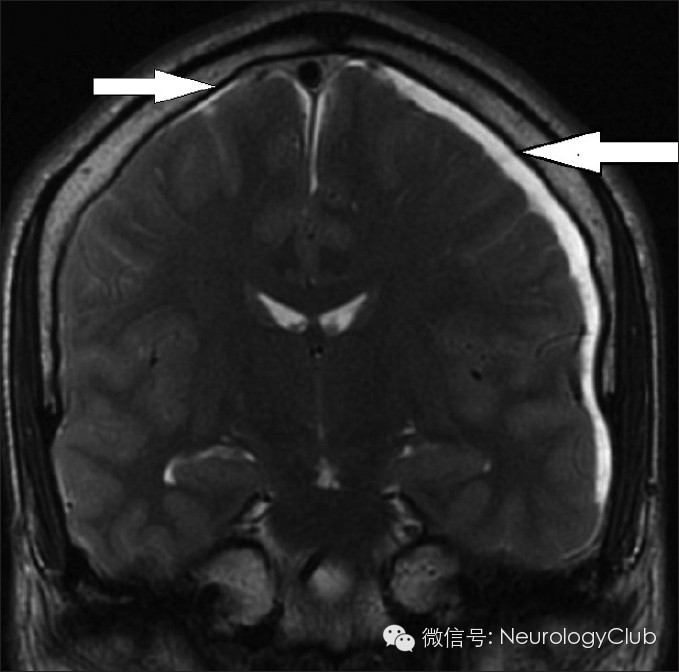

硬膜下积液表现为双侧对称性薄层积液,无占位效应,对下面的脑沟脑裂无压迫效应。

增强扫描时硬脑膜弥漫性增强增厚是颅内低压综合征的最具特征性表现,也是阳性率最高、出现最早的MRI表现。呈不间断的线样增强,无局限性结节,同时经常伴有硬脑膜增厚和皮层静脉的扩张,但从不累及软脑膜。